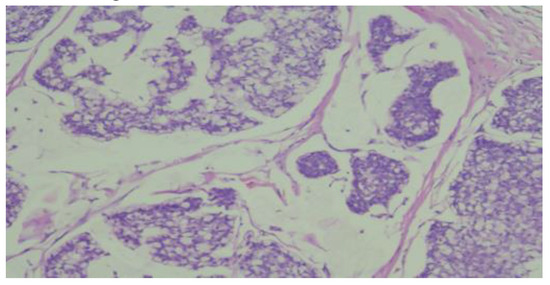

The patient underwent an abdominal CT examination, which described the presence of two accessory spleens measuring 24 mm and 19 mm, respectively, following pancreatectomy of the body and tail and splenectomy. Additionally, a left renal cystic mass measuring 28 mm was detected. Accidentally, a tumor in the right breast in the lowerouter quadrant was observed, measuring 14/15 mm. The high suspicion raised by the abdominal CT led to further imaging investigations, with breast ultrasound con-firming the presence of a strongly hypoechoic spiculated mass measuring 16/13.5 mm, with irregular contours, as shown in Figure 1.

Figure 1. Right breast sonogram shows a hypoechoic mass about 16 x 13.5 mm.

On ultrasound examination, mucinous carcinoma appears as a round or oval mass, isoechoic or hypoechoic compared to subcutaneous fat, often with posterior acoustic enhancement and internal echoes, along with cystic or solid components [].